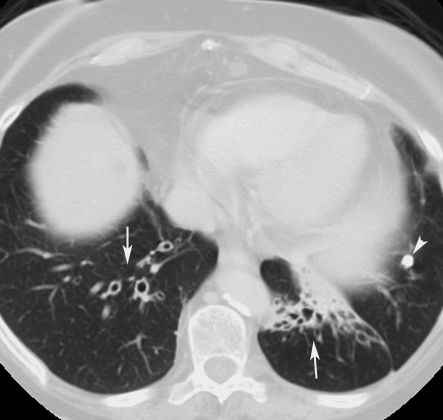

• Arrows point to bronchiectasis of lower lobes. Bronchi are dilated with thickened walls. Normal bronchi are not demonstrable at this level.

• Arrowhead points to calcified granuloma.